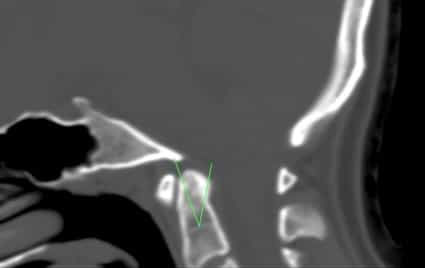

Рис.1 Смещение зуба осевого позвонка на КТ изображении.

Диагноз смещения осевого позвонка может быть поставлен при помощи КТ черепа (Рис.1) или МРТ головного мозга или шейного отдела (Рис. 2).